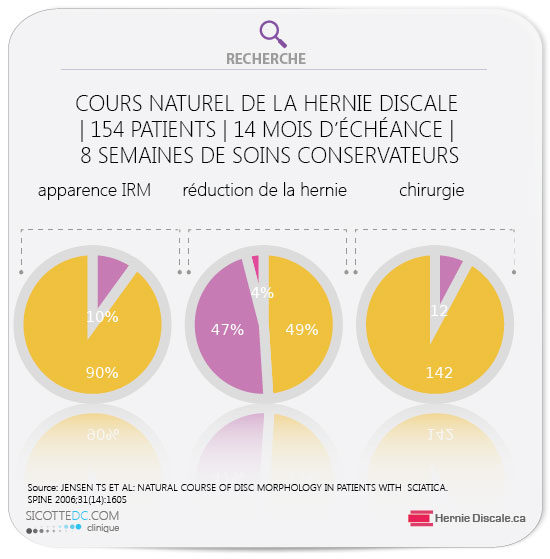

STATISTIQUES – HERNIES DISCALES | TRAITEMENT NATUREL

Les hernies discales symptomatiques n’atteignent que 5 % des patients. De récentes études indiquent que dans environ 63 % des cas d’hernie discale, le cours normal des choses entraînera une autorétraction par voie de rétrécissement de la hernie. Voici une autre étude sur le cours naturel de la hernie discale avec soins naturels (non chirurgicaux) (Natural course of disc morphology in patients with sciatica: an MRI study using a standardized qualitative classification system) démontre que seulement 7 % ont dû avoir recours à l’intervention chirurgicale.

– 90 % démontrent une morphologie dite symptomatique à l’imagerie IRM,

– 47 % du disque symptomatique avait subi une résorption (diminution) naturelle,

– 49 % n’avait pas changé de morphologie,

– 4 % était plus volumineux,

les hommes répondent mieux aux soins

– 12 ont subit une chirurgie,

RÉSORPTION D’UNE HERNIE DISCALE AVEC TRAITEMENT MÉTHODE COX®